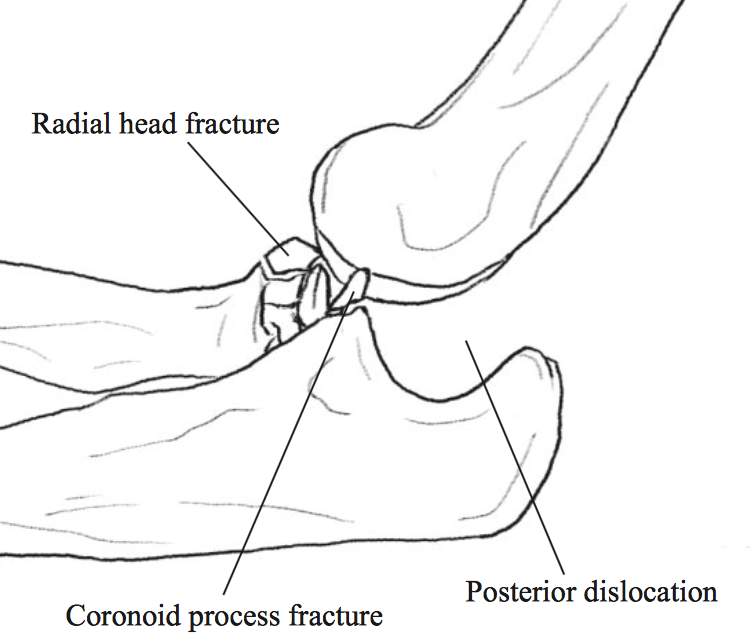

Listen for a click or a palpable pop at the radial head, which. A gentle pull and push and the elbow could be back in place. Often, in addition to a dislocation, there is a fracture with displacement of bone fragments, etc.

Sedation and muscle relaxers may be necessary to correct your elbow dislocation. This clip describes why elbow dislocation is hard to achieve in dogs, but when it occurs, how it is reduced. What are the risk factors for.